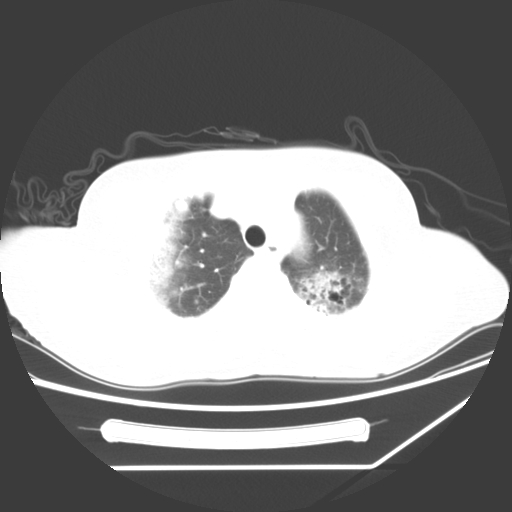

标题: CT25393:病人45岁,咳嗽,吐黄痰带血丝,发热,胸闷月余 [打印本页]

标题: CT25393:病人45岁,咳嗽,吐黄痰带血丝,发热,胸闷月余

1、左肺中央型肺癌并双肺弥漫性转移   2、双肺部感染    3、肺大泡     4、左侧胸腔积液

双侧肺弥漫性病变,可见“空泡征”及“蜂窝征”,考虑肺泡癌可能性大,左侧胸腔积液,考虑胸膜受累可能!

考虑肺泡癌,建议排除感染。

考虑肺泡癌

1)不排除肺泡癌可能。2)左侧胸腔积液。